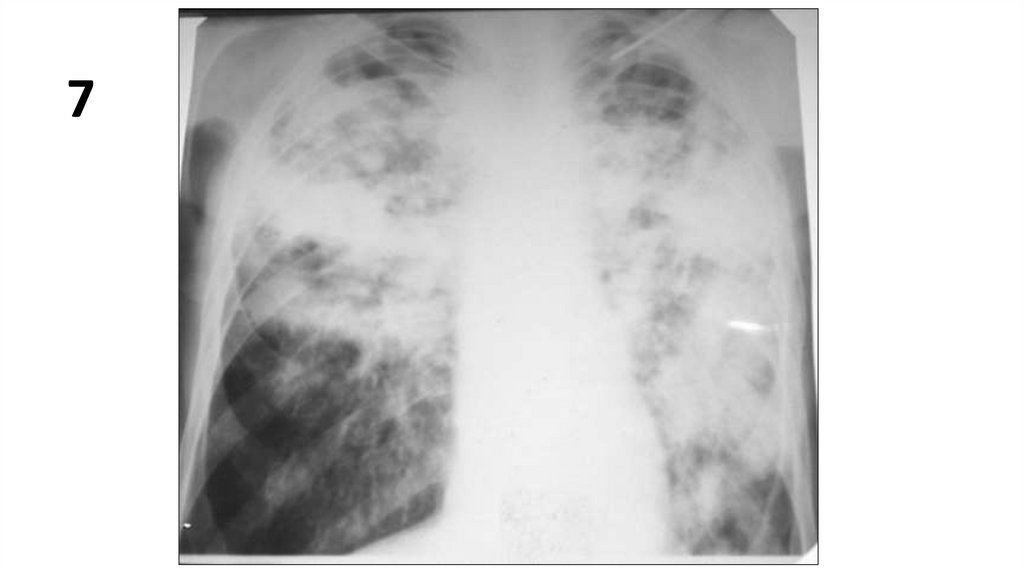

7

9.